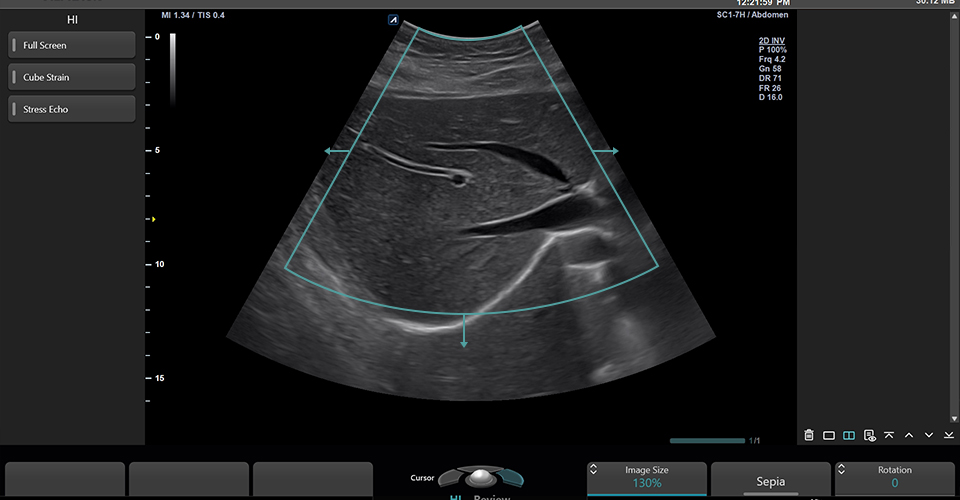

SC1-7H

X+ Crystal Signature™ convex transducer(1~7MHz)

Application:

Abdomen, EM, Gynecology, Obstetrics, Pediatric, Urology